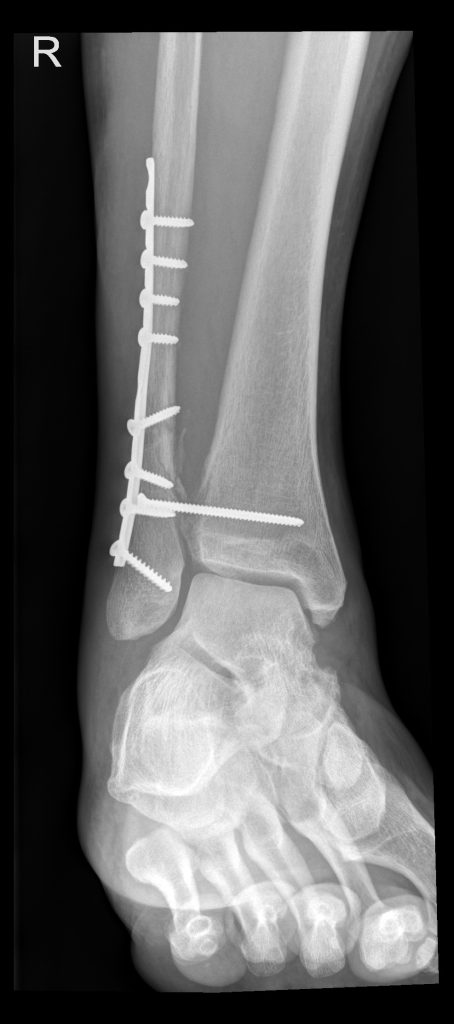

2. Februar 2026 – Röntgen und Ops-Sprechstunde

Danach folgte die Sprechstunde mit dem Orthopäden, Dr. Alexander Ewers, der mich darüber aufklärte, was er am nächsten Freitag zu tun gedenke.

Die lange Schraube kommt raus. Sie hat in den letzten 6 Wochen Schien- und Wadenbein stabilisiert, bis der genähte Syndesmosebandriss ausgeheilt war.

Eine Syndesmose ist eine bandartige Verbindung zwischen zwei Knochen, die aus straffem Bindegewebe besteht und als «unechtes Gelenk» gilt; sie stabilisiert vor allem das obere Sprunggelenk zwischen Schien- (Tibia) und Wadenbein (Fibula) und ermöglicht eine begrenzte Bewegung, wobei eine Verletzung zu Instabilität führt und oft eine operative Stabilisierung erfordert.

Dazu braucht es nur einen Schnitt von ca. 2 cm Länge. Dr. Ewers empfahl mir eine Vollnarkose, weil das Herausdrehen solcher Schrauben oft mehr Kraft erfordert als erwartet. Die Schraube kann fest im Knochen sitzen oder von Narben- und Knochengewebe umgeben sein, sodass beim Lösen deutlicher Zug, Druck und Vibrationen entstehen. Diese Empfindungen lassen sich mit einer Teilnarkose/Spinalanästhesie nicht immer vollständig ausschalten und sind sicher sehr unangenehm, selbst wenn sie nicht direkt schmerzhaft sind. Eine Vollnarkose sorgt für vollständige Muskelentspannung, verhindert unwillkürliche Bewegungen und nimmt auch die belastenden Geräusche und Erschütterungen komplett aus dem Erleben heraus. Zudem ist der Eingriff in seiner Dauer nicht immer exakt vorhersehbar, was sich unter Vollnarkose leichter und sicherer handhaben lässt.

Heute ist also der grosse Tag, an dem der erste Schritt zurück zur Normalität geschehen soll: Die Stellschraube, die bis zur Verheilung des Syndesmosebandes das Wadenbein am Schienbein fixierte, kann endlich raus. Damit ist auch wieder Torsion möglich und ich darf wieder 100% belasten. Wie gesagt, es ist ein erster Schritt und die Reha wird noch einige Zeit brauchen.